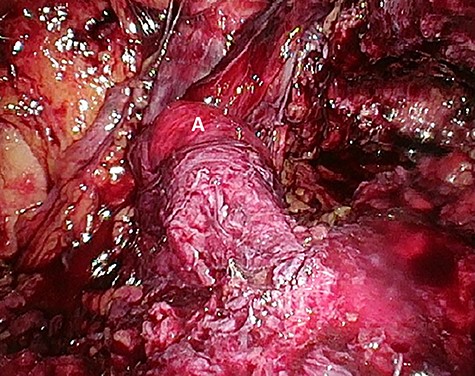

Considering the patients’ comorbidities (obesity, Type 2 diabetes mellitus), a re-TAPP was performed to avoid possible wound complications. The recurrent hernia was presumably confirmed as a lateral inguinal hernia. After dissecting dense fibrotic scar tissue around the previous mesh preperitoneally, the hernia sac was released. A large spermatic cord lipoma was found and dissected (Figs 1 and 2). A new mesh (BARD® 3D Light Mesh, 10 × 15 cm) was inserted.

Dissection of the large spermatic cord lipoma with attached fibrotic tissue.